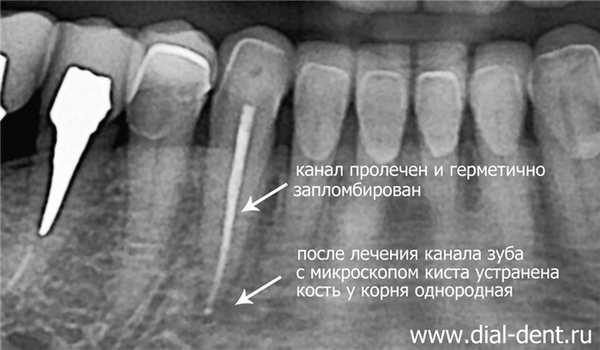

Решение: выполнено лечение канала зуба под микроскопом, в следствие чего полностью удалена киста зуба.

Киста зуба лечение

Киста зуба долгое время была показанием к удалению зуба. Только так можно было предотвратить распространение воспаления в кости на корни соседних зубов, тем самым сохранив остальные зубы. Современные стоматологи используют микроскоп и специальные эндодонтические инструменты, которые проходят в самые тонкие каналы зуба. В «Диал-Дент» лечат зубы только с микроскопом. С применением микроскопа стало возможно лечение кисты зуба без удаления. Нехирургическое лечение кисты зуба состоит в лечении корневых каналов, устранении воспаления внутри зуба, что останавливает воспаление у корней, герметичной пломбировке каналов.

Для лечения кисты зуба потребовалось два посещения клиники. В первое посещение канал был очищен от воспаленных тканей, промыт противомикробными растворами, в канал помещено лекарство для полного уничтожения инфекции в зубе и у корней, зуб закрыт временной пломбой. Примерно через 2 недели был второй визит. Канал зуба промыт, просушен. Выполнен рентген зуба, чтобы определить точную длину канала. Канал герметично запломбирован горячей гуттаперчей (качество пломбировки проверяется рентгеновским снимком). Рентген зуба проводится прямо в кресле, пациенту не надо никуда ходить, так как рентгеновский аппарат есть в каждом кабинете «Диал-Дент». Полость зуба закрыта пломбой.

На КТ зубов, выполненной через 6 месяцев после лечения кисты зуба видно, что кость около корня восстановилась, никаких признаков кисты больше нет: